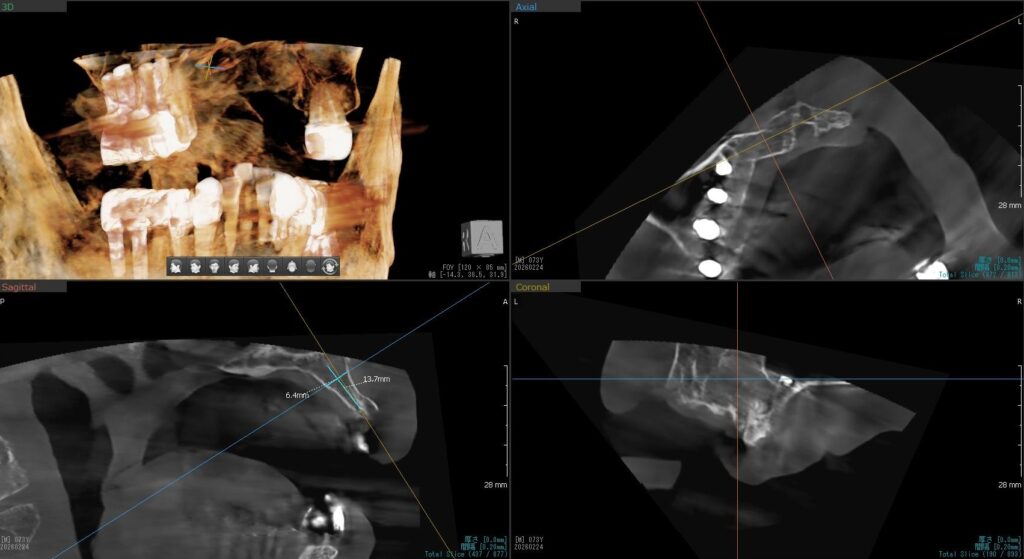

今回の患者様は、以前にもインプラントを植立された経験がある方で、今回もインプラント植立を希望されたので、右上1番目・2番目、左上1番目、2番目~6番目の合計7本の植立が決まりました。

ドリルの先端を細い物から徐々に大きい物に変えながら、植立するインプラント体のネジの部分を除いた胴の部分の太さに合わせた大きさの穴を開けていきます。

開けた穴に、専用道具を使ってネジを締めるように長さ2センチ程のインプラントを骨に埋め込んでいきます。